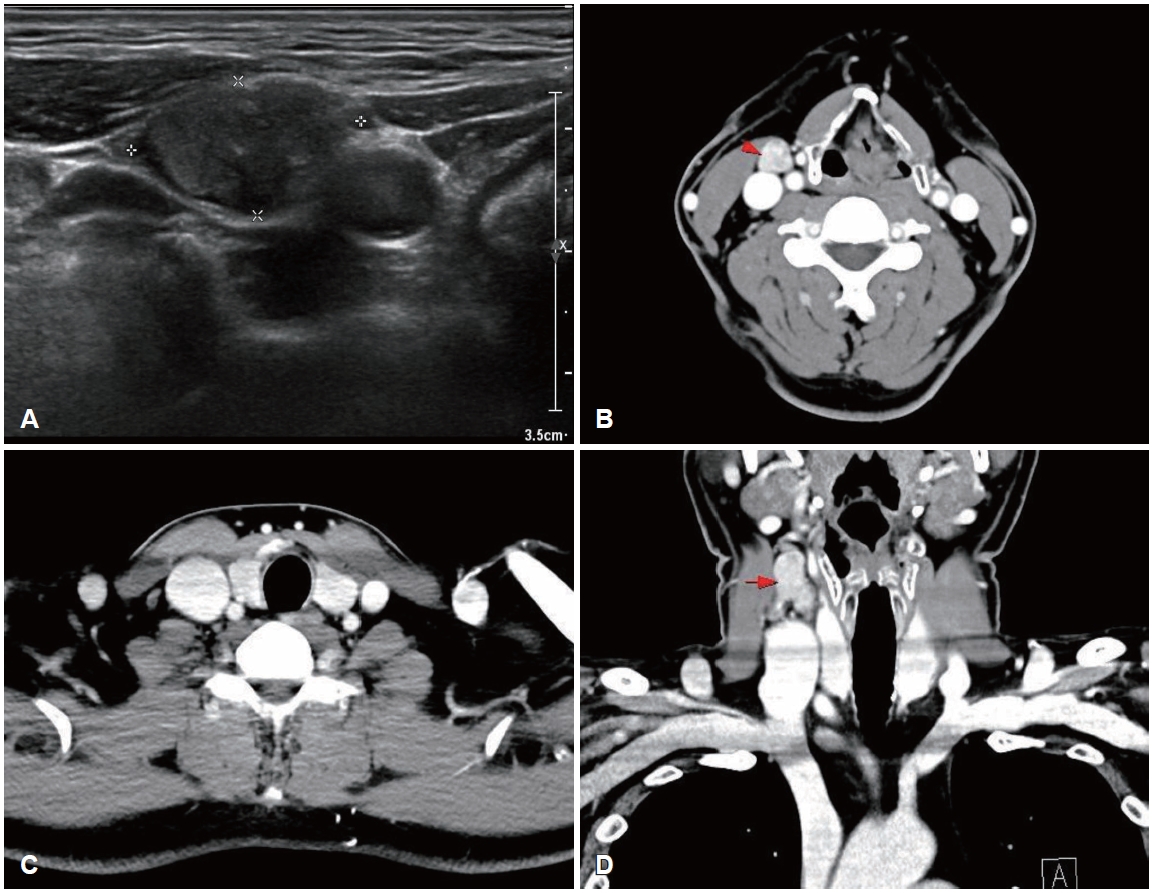

CaseA 50-year-old male was referred to our outpatient clinic after incidentally detected cervical masses during an ultrasound-guided procedure for neck pain at a local clinic 3 weeks ago. Local ultrasonography revealed heterogeneous masses of varying sizes in the right neck. He was asymptomatic, had no underlying disease, and no palpable mass was detected on physical examination. On the day of presentation, repeat ultrasonography demonstrated a 2.04×1.11 cm oval-shaped, well-defined, heterogeneously hypoechoic mass with low vascularity and loss of the fatty hilum at right level III (Fig. 1). The sonographic appearance did not specifically suggest metastatic PTC; rather, a neurogenic tumor was favored because of the mass morphology and perivascular location. No suspicious lesions were identified in the thyroid parenchyma or salivary glands. Because pathologic confirmation was required to guide management, fine-needle aspiration of the mass was performed simultaneously and revealed metastatic PTC; nuclear enlargement, multiple nuclear pseudoinclusions, and grooves were noted with positive immunohistochemical staining for thyroid transcription factor-1 (Fig. 2).

The biopsy report was explained to the patient and after counseling, the patient elected surgery to remove a presumed occult thyroid primary and any additional nodal disease. Contrast-enhanced neck CT was subsequently obtained to evaluate the thyroid gland and additional cervical metastases before surgery and no other imagaing study was performed. No definite lesion was identified in both thyroid lobe, and only a single enlarged right level III lymph nodes were observed (Fig. 1). Total thyroidectomy with right selective neck dissection (levels II-IV) and central compartment node dissection was performed in accordance with 2015 American Thyroid Association (ATA) guidelines to remove hidden malignancy in thyroid gland, to enable postoperative serum thyroglobulin (Tg) monitoring for recurrence detection and to allow radioactive iodine (RAI) ablation if needed [3]. A firm 3.0×2.0 cm mass was noted at right level III, and a firm 0.5 cm nodule at the superior thyroid isthmus was suspicious for micro-PTC. Both recurrent laryngeal nerves were identified and preserved. Pathologic examination showed no abnormality in either thyroid lobe, and the palpable isthmic nodule represented nodular hyperplasia (Fig. 3). Total 11 lymph nodes of 28 were found metastatic PTC and single node with extranodal extension (ENE) at right level II was identified with 18 mm of largest dimension; metastatic involvement included 5 level VI nodes of 9 without ENE, 5 right level II nodes of 7 with ENE, and 1 right level III node of 8 without ENE; no level IV nodes were involved (0/4). Postoperatively, both the resected lymph nodes and the isthmic nodular hyperplasia were tested for BRAF mutation, and all results were negative.

NotesAuthor Contribution Conceptualization: Yong-Dae Kim, Si-Youn Song. Data curation: Gi Moon Yoo. Formal analysis: Gi Moon Yoo, Jaebeom Park. Investigation: Yong-Dae Kim. Methodology: Gi Moon Yoo, Jaebeom Park, Si-Youn Song. Project administration: Gi Moon Yoo, Jaebeom Park. Supervision: Yong-Dae Kim, Si-Youn Song. Validation: Si-Youn Song. Visualization: Yong-Dae Kim, Si-Youn Song. Writing—original draft: Gi Moon You. Writing—review & editing: Gi Moon Yoo. Fig. 1.Preoperative ultrasonography and CT findings. A: An oval-shaped, well-defined, heterogeneously hypoechoic mass measuring 2.04×1.11 cm with low vascularity and loss of the hilum is present at right cervical level III. B-D: Axial (B and C) and coronal (D) contrastenhanced CT images show an approximately 14×15×21 mm, well-marginated, heterogeneously enhancing solid mass-like lesion at right level III (red arrows) and no definite space-occupying lesion in either thyroid lobe. Fig. 2.Histologic features of the right level III mass from fine-needle aspiration. A: Histopathology shows nuclear enlargement, multiple nuclear pseudoinclusions, and grooves, consistent with metastatic papillary thyroid carcinoma (hematoxylin-eosin, 400×). B: Immunohistochemical staining for thyroid transcription factor-1 was positive in the tumor cells (hematoxylin-eosin, 200×). Fig. 3.Histologic features of the thyroid gland. Histopathology showed 0.2×0.2 cm nodular hyperplasia at thyroid isthmus without features of papillary thyroid carcinoma (hematoxylin-eosin, 40×). Fig. 4.Postoperative positron emission tomography-CT and thyroid scan findings. A and B: Uneven 18F-fluorodeoxyglucose uptake in the anterior neck and mild uptake in both lateral necks suggest postoperative changes and reactive lymph nodes. No other hypermetabolic lesions suggest metastasis to other organs. C: Postoperative Tc-99m pertechnetate thyroid scan shows no significant radioactive accumulation. Table 1.Previous reports of ATA intermediate-risk metastatic PTC without primary tumors